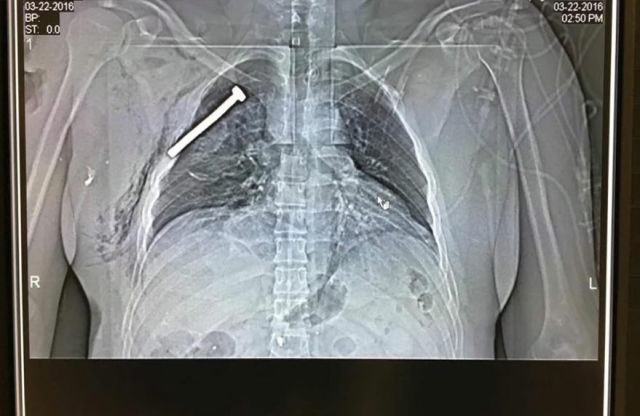

Лікарі показали журналістам рентгенівські знімки одного з прооперованих пацієнтів, у грудях якого застряг величезний шуруп, передає «tvn24.pl».

Цю інформацію підтверджують в іншій лікарні на східній околиці Брюсселя, куди госпіталізували 13 поранених. Більшість з них мали у своїх тілах різні металеві предмети.

Це свідчить, що терористи начинили бомби цвяхами, щоб збільшити їх ударну силу і щоб, якомога більше людей отримали поранення. Відзначимо, що подібну тактику у часи Євромайдану застосував «Беркут».